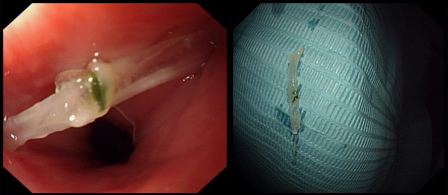

张金宝主任简单扼要的询问了老人的基本情况和发病过程,“吸氧、安装心电和氧饱和监护!”张金宝主任协助患者平卧在治疗床上后利落地带上手套,操控着胃镜准备进入食道夹取异物。看似粗长的胃镜在张主任的操作下灵巧地运动着,过会厌,进食管,发现一根1公分多的鱼刺卡食管上段,由于老人家属之前各种不科学的方法,鱼刺已经刺入食管壁内,张金宝主任迅速由内镜进入异物钳,灵巧的反复拨弄,将鱼刺完整的取了出来。之后在内镜下仔细观察了并确认伤口没有明显出血和穿孔后,小心轻柔地退出内镜。

“还好送医及时,鱼刺只是刺入肌层,并没有造成食管穿孔,不然后果不堪设想。现在让老人先在这休息留观一下,没有什么问题,也不需要住院了,但是回去要注意休息和饮食。”张金宝主任向老人家属交代着病情。此时,老人也因为鱼刺的取出,不适感也消失了。从进内镜中心到鱼刺取出,整个过程仅仅10多分钟!老人没有大碍了,家属们纷纷感谢着张金宝主任的帮助,称赞着手术的及时和高效,“这是医护人员应该做的。”张主任笑着,走到老爷子前嘱咐了一些以后应该注意的事项,护送一行人离开了内镜中心。